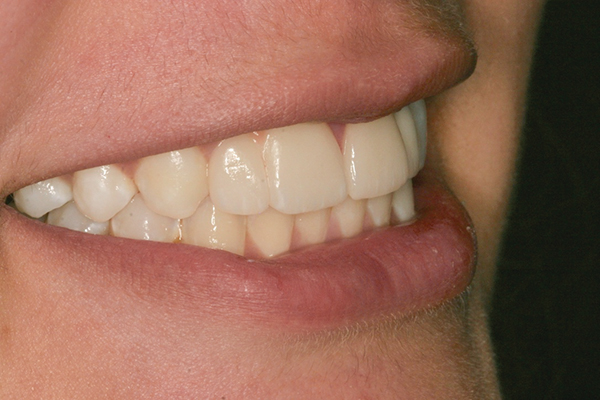

Fig 13 to Fig 16. Post-treatment photographs.

When the patient was 19 years old, the lithium-disilicate veneers and the ceramic crown were tried in and evaluated. Following modification, the veneers were carefully cemented with an adhesive resin cement following application of silane to the intaglio surfaces, etch of the enamel, and application of primer and adhesive. The intaglio surface of the implant crown was treated with a porcelain etch product and silane, and the crown was cemented with carboxylate luting cement with 1 drop of water for retrievability. A paintbrush was used to apply a thin layer of cement to minimize excess. Any excess cement on the veneers and crown was meticulously removed, and the margins and occlusion were carefully checked. The patient returned 2 weeks later (Figure 13 through Figure 18) for a review of her oral hygiene and for fabrication of a nightguard. The patient was happy with the esthetic result and exclaimed she had been stopped on the street and told she had a beautiful smile.